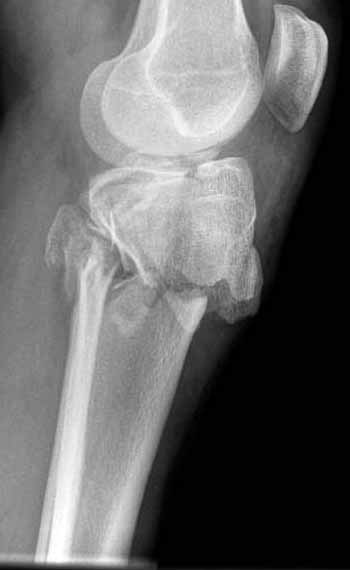

Двухколоннный перелом тибиал плато с вовлечением проксимального диафиза. Внутрисуставной компонент без смещения, и такой перелом можно лечить любым из описанных методов, о которых говорят наши коллеги.

Как понял, аппарат Илизарова не рассматривается предпочтительным для фиксации методом, хотя на фоне отека было бы идеальным для данного перелома. Для пластины требуется идеальная кожа, иначе наличие “суперсовременных имплантов” не поможет, и могут развиться серьезные осложнения.

В основном пластины рассчитаны на латеральную поверхность, потому что с латеральной стороны больше мягкотканая подушка, а также через латеральную колонну проходит ось конечности, что немаловажно в удержании оси от деформации.

Частая ошибка, когда фиксацию двух колонного перелома проводят одиночной пластиной, т.е с одной стороны, и такая фиксация не удерживает, происходит вторичноое смещение. Необходимо нейтрализовать второй пластиной или дополнительным наружным фиксатором.